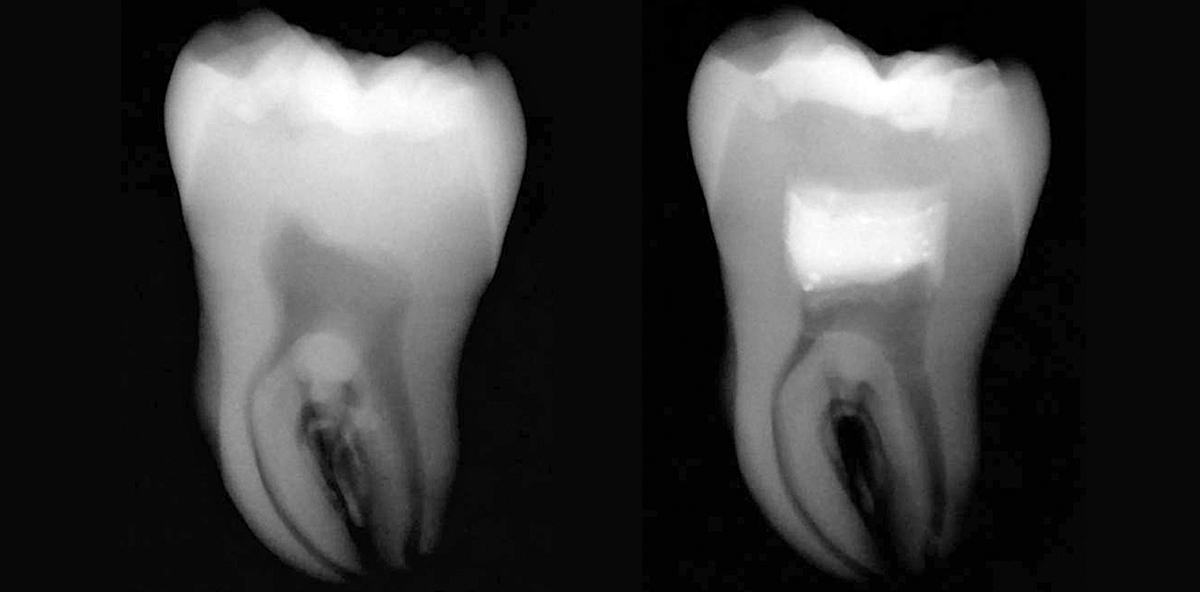

Die Abbildungen 8 bis 11 zeigen eine vitale Pulpatherapie mit MTA+ in Zahn 38 bei einem 60-jährigen männlichen Patienten. Der Zahn an sich war klinisch symptomlos und sensibel auf Kälte. Da der Ausschnitt der Bissflügelaufnahme schon ein hohes Pulpaeröffnungsrisiko zeigte, wurde mit dem Patienten zudem auch das Vorgehen bei einer Nerv-Eröffnung erörtert. Für den Patienten kam eine Wurzelkanalbehandlung an 38 nicht infrage, aber er war offen für eine Kompositrestauration mit MTA.

Nach Anlegen von Kofferdam und anfänglicher Entfernung der alten Füllung, löste diese sich komplett und eine wohl schon länger mit dem Mundraum verbundene Pulpa war sichtbar. Nach Behandlung des Kofferdams mit CHX 2 % folgten nun nachkommende Schritte: